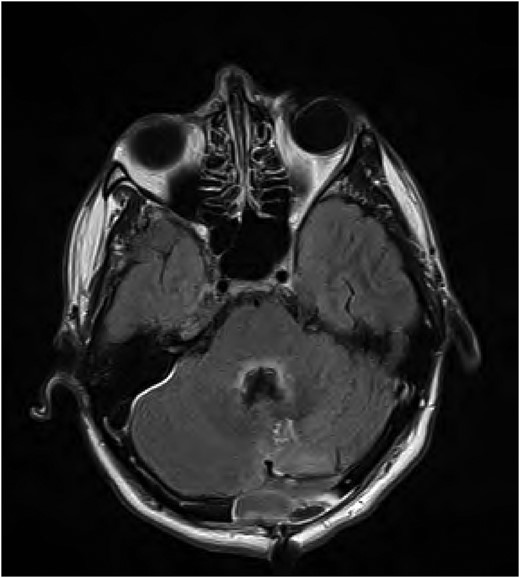

Magnetic resonance imaging (MRI) of the brain performed Day 2 post procedure showed fluid-attenuated inversion recovery sequence (FLAIR) abnormality within the floor of the fourth ventricle, on the dorsal pons, involving the facial colliculus (Fig. 1).

FLAIR MRI brain showing high signal abnormality in the floor of the fourth ventricle.